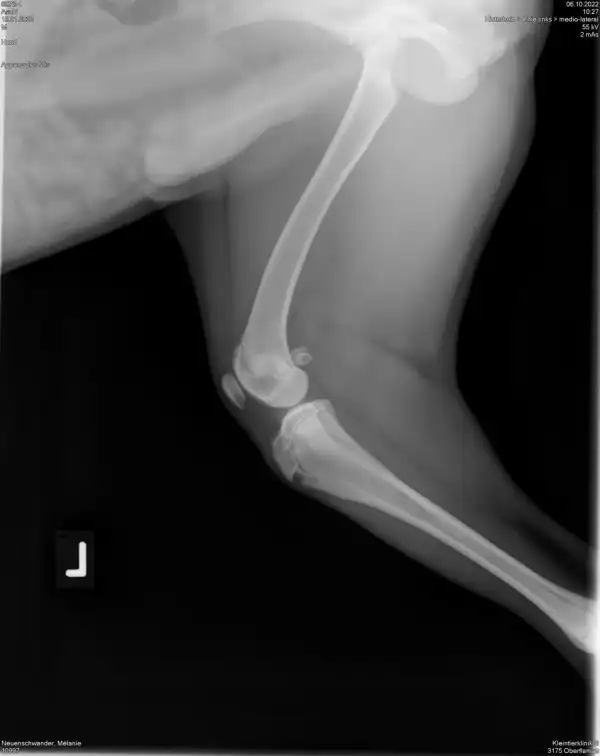

Aschi muss an beiden Knien Operiert werden.

Aschi hat in den elf Monaten seines Lebens noch nicht viel Freude gehabt. Mit gerade mal sieben Wochen hatte er einen schweren Unfall. Seither versuchen wir alles, dass Aschi ein normales Schmerzfreies Hundeleben leben kann. Leider steigen die Kosten immer höher und die teuren Knieoperationen stehen noch bevor. Da wir ihn direkt nach dem Unfall abgeholt haben und zum Notfall Tierarzt mussten, konnten wir keine Versicherung abschliessen.